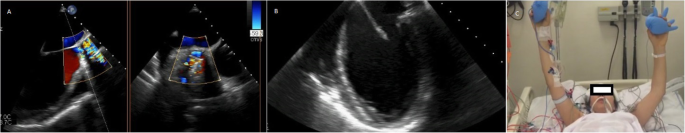

Patient is a petite 35-year-old vegan female with past medical history of systemic lupus erythematosus (SLE), antiphospholipid syndrome (APS), and deep vein thrombosis complicated with pulmonary embolism for which she received rivaroxaban. On routine medical examination, while she was completely asymptomatic, a holosystolic murmur was detected, thus, echocardiography was requested. It revealed a dilated left ventricle with mild hypertrophy and an ejection fraction of 58%. Her aortic leaflets were thickened with limited mobility, her maximum aortic velocity was 4.36 m/s, and the mean gradient was 45 mmHg. A severe regurgitant flow was at the aortic valve confirming severe aortic insufficiency (AI) and moderate aortic stenosis (AS). Mixed aortic valve disease was diagnosed and due to her clinical background, surgery was decided, nonetheless anxiety and fear caused her to refuse surgery. One year passed and although she remained asymptomatic, her condition worsened, maximum aortic velocity was 5.36 m/s, the mean gradient was 60 mmHg, and aortic valve area was 0.9 cm2. Also noted was an increase in the left ventricular diastolic diameter due to severe aortic Insufficiency (Fig. 1a). After great help from her family and psychology treatment, surgery was accepted. Sternotomy and cardiopulmonary bypass (CPB) were completed after a dose of 300 U/kg was administered and the ACT (activated clotting time) was over 480 s, the ACT was monitored every 30 min. Cardiac arrest was achieved via antegrade and retrograde cardioplegia, the temperature was kept at 35 C and cold cardioplegia was administrated every 10 min. Aortotomy was done. The aortic valve was visualized, revealing fibrous and stenotic aortic leaflets. The leaflets were excised, and a 17-mm prosthetic aortic valve was placed (St. Jude Medical, Inc., St. Paul, Minn) after we measured her aortic annulus diameter (18 mm) (Fig. 1b). Both coronary vessels were identified and spared during the valve replacement. Once the valve was sewn and placed, the aortotomy was closed with a 5–0 polypropylene suture in a two-layer fashion. Before removing the aortic cross-clamp warm blood retrograde cardioplegia was given. The cross-clamp was removed, and the heart reverted in sinus rhythm. With a transesophageal echocardiogram (TEE) the prosthetic valve was evaluated and didn’t exhibit any problems (Fig. 2a). The patient was weaned off CPB using a 50 mg test dose of protamine. With no hemodynamic instability from this dose, the rest of the protamine was given slowly over 15 min. While finishing the procedure as the sternal wires were placed, the patient suddenly suffered from severe hypotension, bradycardia, and sudden cardiac arrest. The sternal wires were removed, and cardiopulmonary resuscitation was started immediately with open cardiac massage and repeated direct defibrillation with 20 joules, heparin was given, aortic and atrial cannulation was done during the cardiac massage and the patient was placed again under CPB. Since the heart had multiple zones of hypokinesia and akinesia in both ventricles. ECG at that time registered pulseless electrical activity. Using TEE, we confirmed regional wall motion abnormalities in both ventricles (Fig. 2b and Supplementary Video (1)). The aortic prosthesis had a normal function and we suspected a coronary perfusion problem. Since it was difficult to locate the exact coronary lesion, we decided to perform an immediate coronary artery bypass graft (CABG) surgery. We used saphenous vein grafts to the left anterior descending and the right coronary arteries. The myocardium showed signs of definite clinical improvement following revascularization. Inotropic and vasoactive agents were partially weaned off along with CPB, the patient was transferred to the intensive care unit for close monitoring. Neurological complications were suspected due to the cardiac arrest, nonetheless, the patient satisfactorily recovered from the procedure without any neurological deficits. Her postoperative course was uneventful despite developing posterior wall MI (myocardial infarction) with preserved ejection fraction, she was fully aware on her first postoperative day and never showed signs of neurological complications (Fig. 2c and Supplementary Video (2)). Anticoagulation was managed with low-molecular-weight-heparin and warfarin was continued until the international normalized ratio (INR) achieved a value ranging between 2.5 and 3.5. She was discharged on her eighth postoperative day. Anticoagulation (Unfractionated heparin and a vitamin-K antagonist) was difficult due to her diet, but she remained on close follow-up controls, with hematologist. A Computed tomography (CT)-coronary angiogram at that time revealed total ostial obstruction of both coronary arteries trunks, and adequate flow through both saphenous vein grafts. On follow-ups, patient was doing well (Fig. 3a, b).